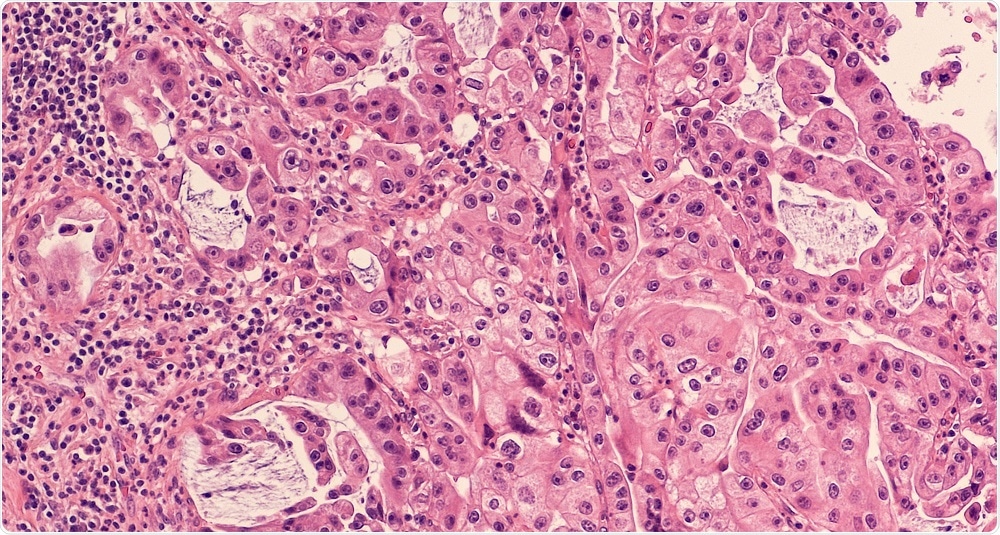

The cancer we are working on is called pancreatic ductal adenocarcinoma (PDAC), a very aggressive cancer of the pancreas.

H&E Staining of a Pancreatic Adenocarcinoma Sample. Credit: David Litman/Shutterstock.com